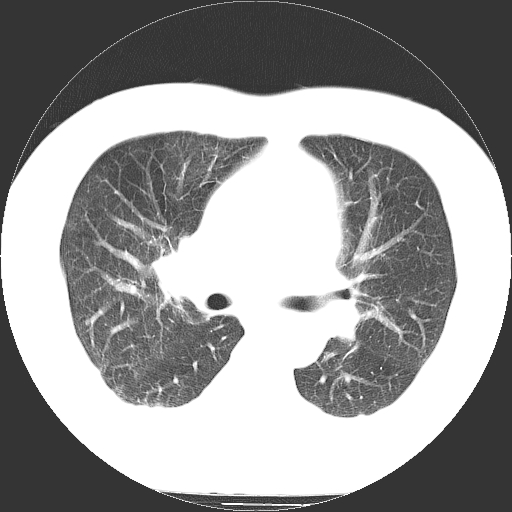

男,65岁,咳嗽、咳痰、发热5天。

慢支 肺间质纤维化合并感染!

支气管扩张合并感染,胸膜肥厚

考虑慢支并感染,肺间质纤维化。

两肺间质性炎症并感染

慢支,肺心病

支持慢性支气管炎伴感染,双侧少量胸腔积液.

两肺间质纤维化,支扩合并感染,双侧胸腔积液

感染,肺间质纤维化。

慢支 肺间质纤维化合并感染

支持慢性支气管、肺间质纤维化合并感染。

慢性支气管炎并感染,支扩,双侧少量胸腔积液.